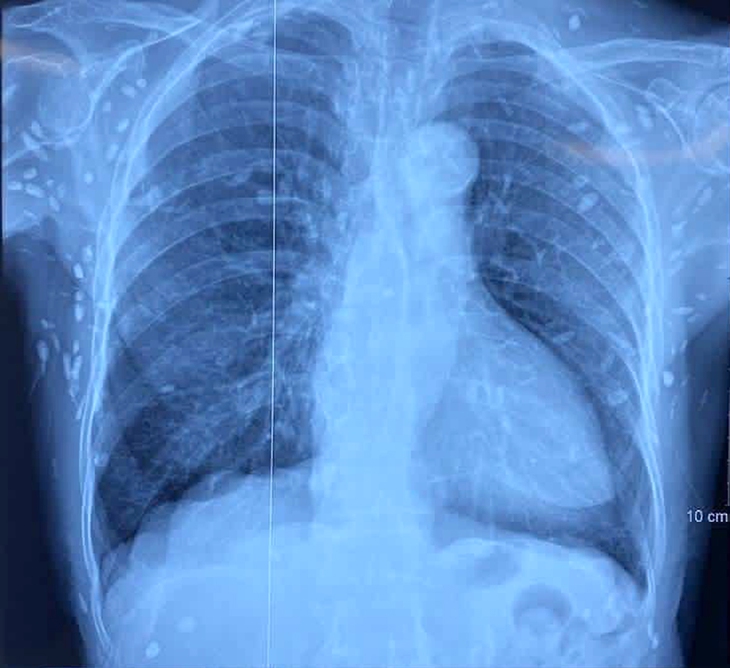

Người bệnh được chẩn đoán nhiễm ấu trùng sán dây lợn. Hình ảnh cắt lớp vi tính sọ não và X-quang ngực cho thấy rất nhiều nốt cản quang trong nhu mô não và dưới da vùng ngực - bụng.

Như người bệnh nữ ở Viện lâm sàng các bệnh truyền nhiễm xuất hiện một số u cục với kích thước tương ứng có thể sờ thấy dưới da vùng ngực và cánh tay của người bệnh.

Chụp X-quang xương đùi, CT-scan ngực tầm soát tổn thương ở cơ quan khác thì phát hiện vô số nang sán dải còn sống hoặc đã bị hóa vôi "ẩn nấp" trong não, nhu mô phổi và trong da, cơ trên toàn bộ cơ thể.